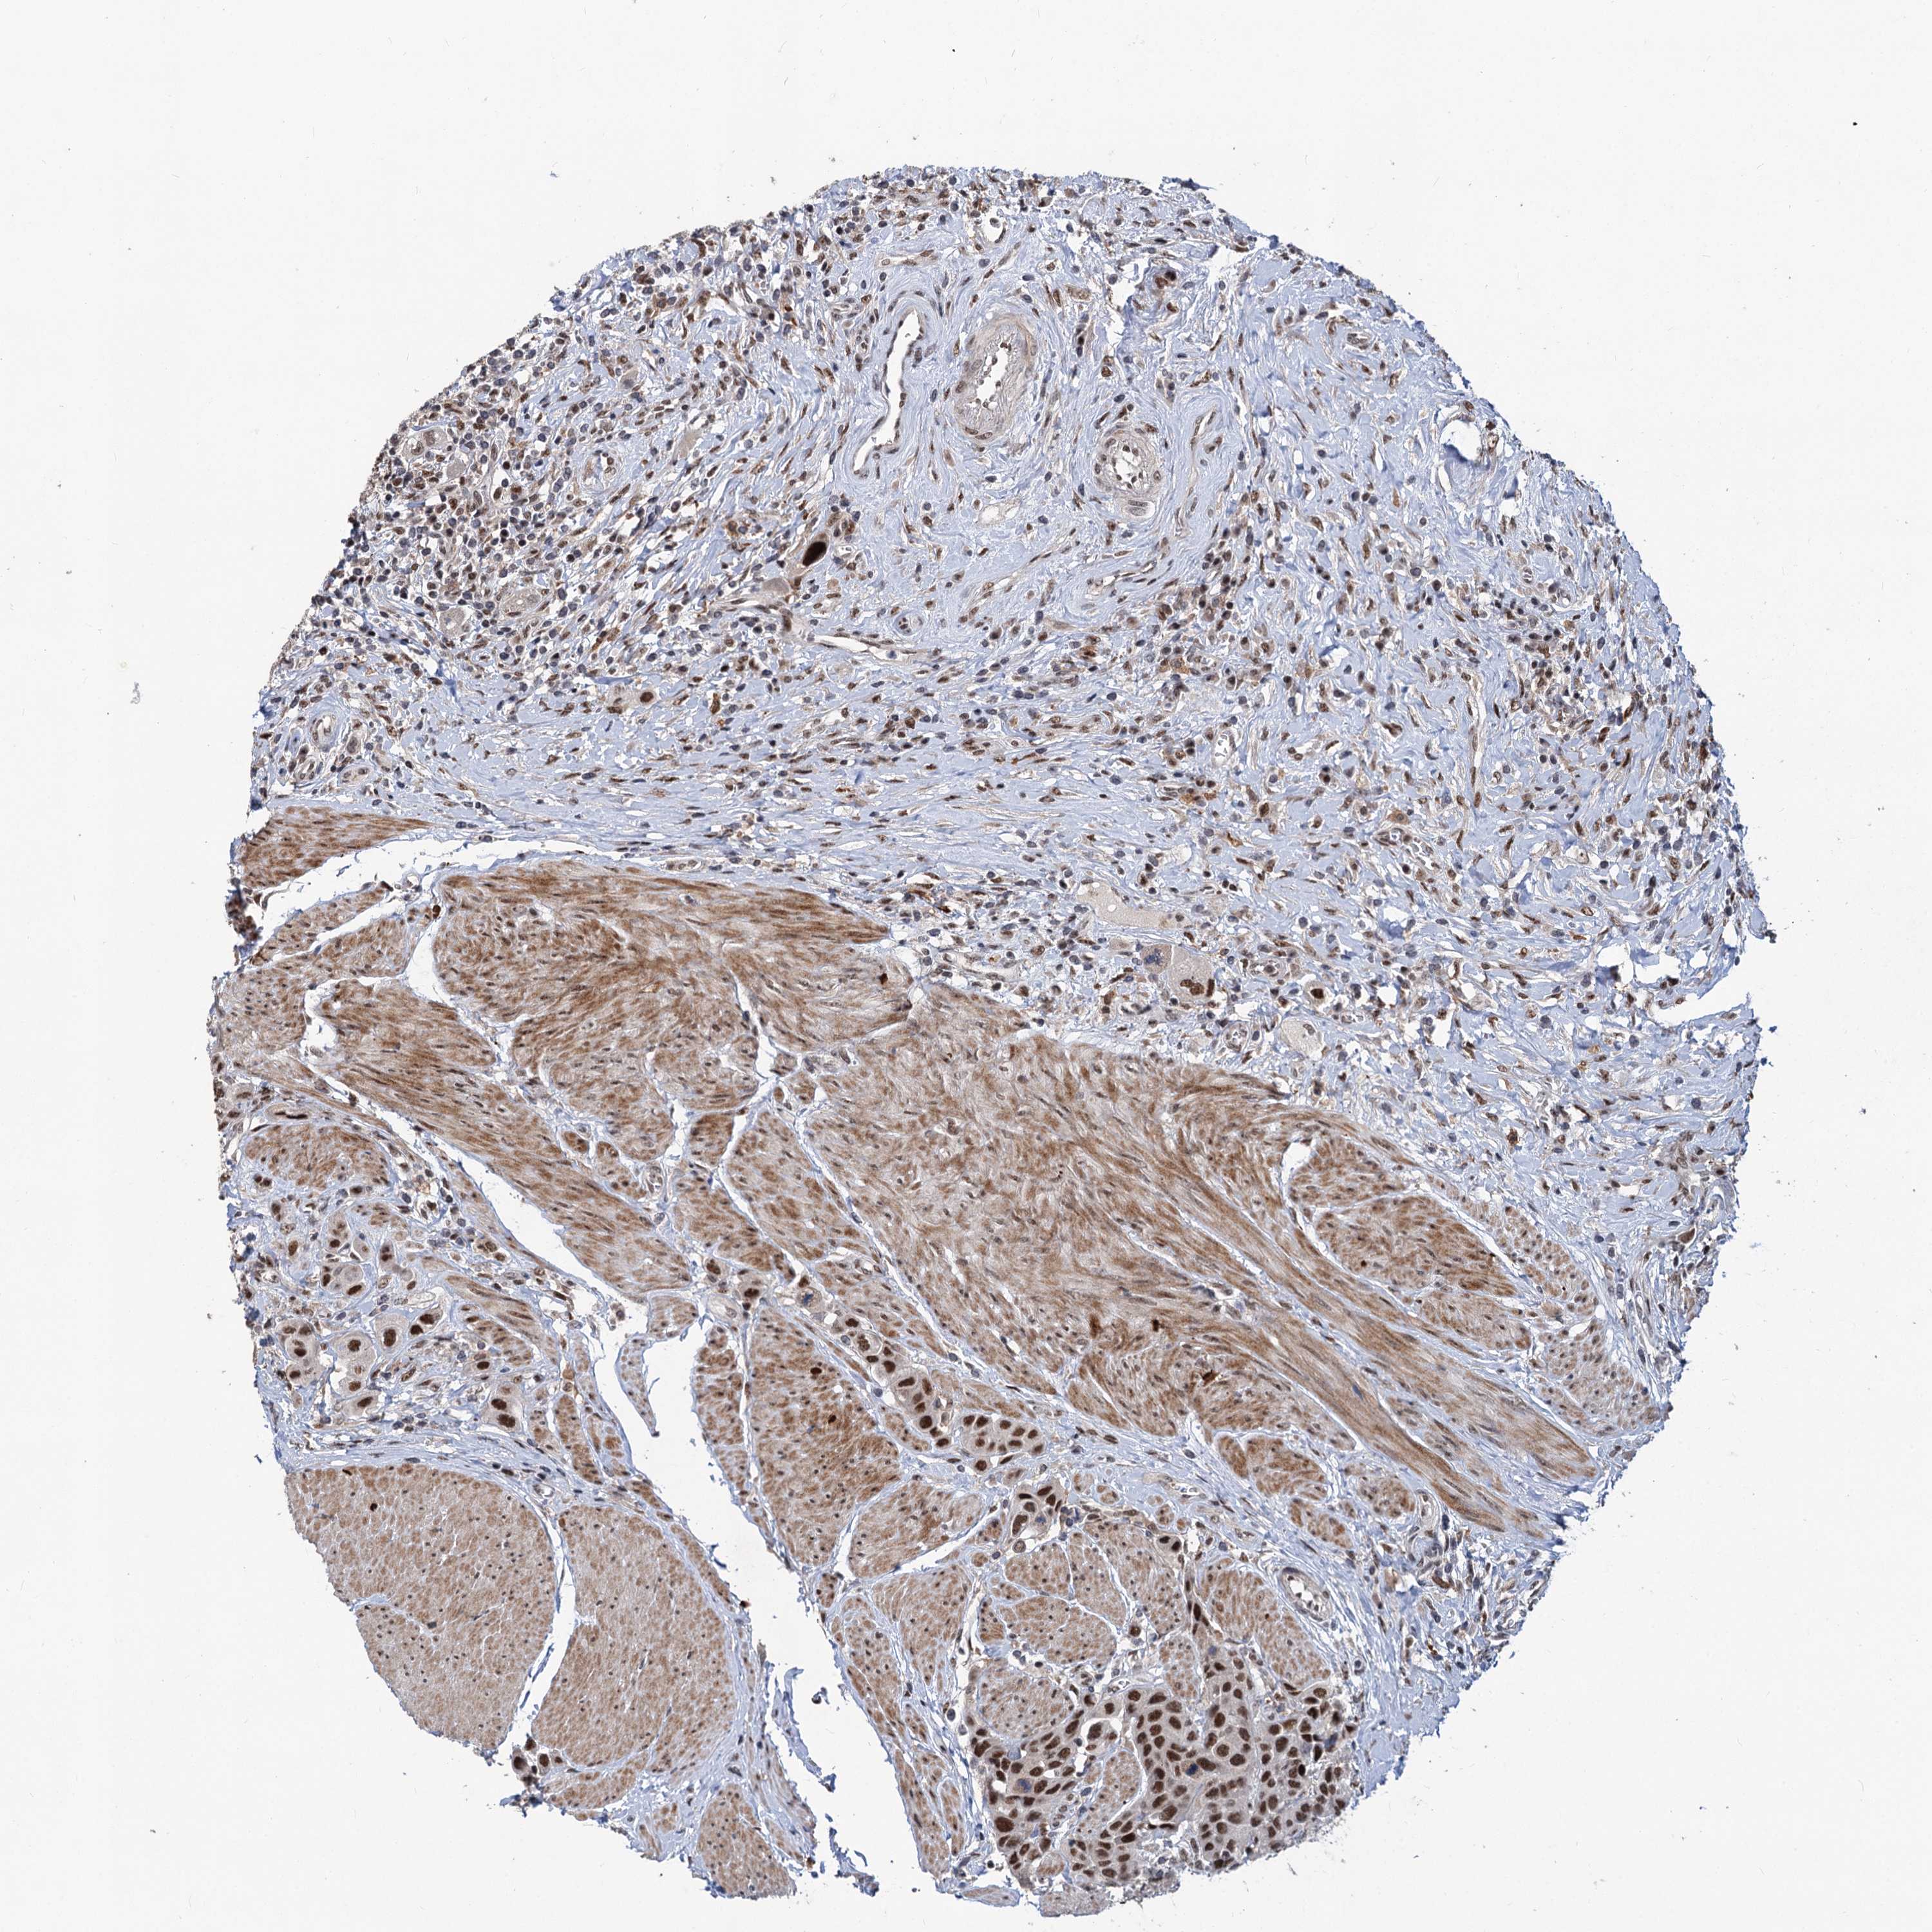

UROTHELIAL CANCER - Protein expressioni

A mouse-over function shows sample information and annotation data. Click on an image to view it in a full screen mode. Samples can be filtered based on level of antibody staining by selecting one or several of the following categories: high, medium, low and not detected. The assay and annotation is described here.

Note that samples used for immunohistochemistry by the Human Protein Atlas do not correspond to samples in the TCGA dataset.

Antibody stainingi

Antibody staining in the annotated cell types in the current human tissue is reported as not detected, low, medium, or high, based on conventional immunohistochemistry profiling in selected tissues. This score is based on the combination of the staining intensity and fraction of stained cells.

Each image is clickable and will lead to virtual microscopy that enables deeper exploration of all samples and also displays staining intensity scores, fraction scores and subcellular localization as well as patient and tissue information for each sample.

Antibody HPA038779

Staining

High

Medium

Low

Not detected

Intensity

Strong

Moderate

Weak

Negative

Quantity

>75%

75%-25%

<25%

None

Location

Nuclear

Cytoplasmic/membranous

Cytoplasmic/membranous,nuclear

Urothelial carcinoma, High grade

Urothelial carcinoma, Low grade